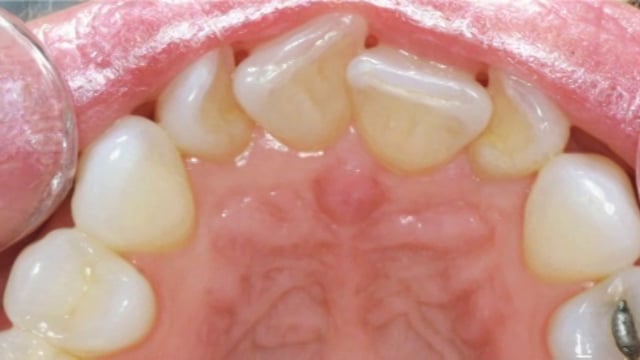

Intra-Oral Camera

We provide our patients with an intra-oral video examination. This allows both the doctor and the patient to see the condition of the mouth at the same time, then discuss treatment options.